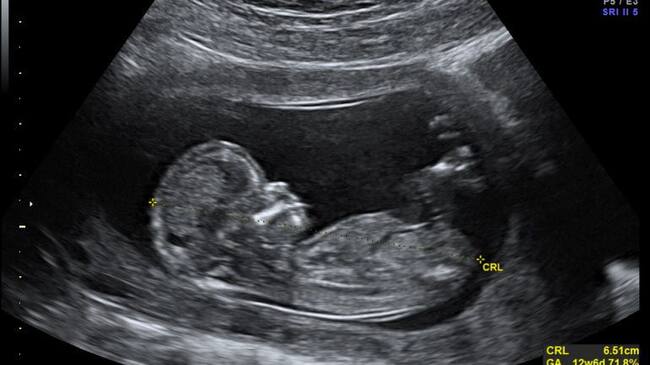

La ecografía sirve para detectar problemas en el crecimiento de los huesos de los fetos durante su periodo de gestación.

La enfermedad de los “huesos frágiles” se llama oficialmente osteogénesis imperfecta y está causada por un error en el ADN del feto en su desarrollo dentro del útero de la madre, que impide la presencia del colágeno necesario para que los huesos se formen de manera adecuada.